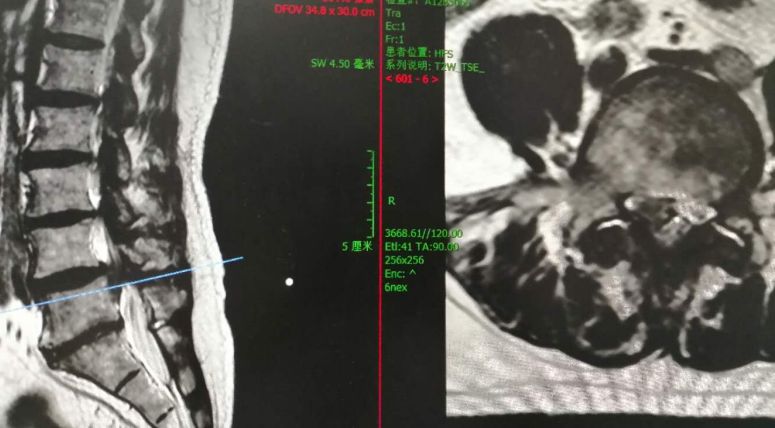

术前磁共振显示腰4/5椎间盘极重度向下脱出游离

术前(左)术后(右)对比显示,游离髓核组织取出干净